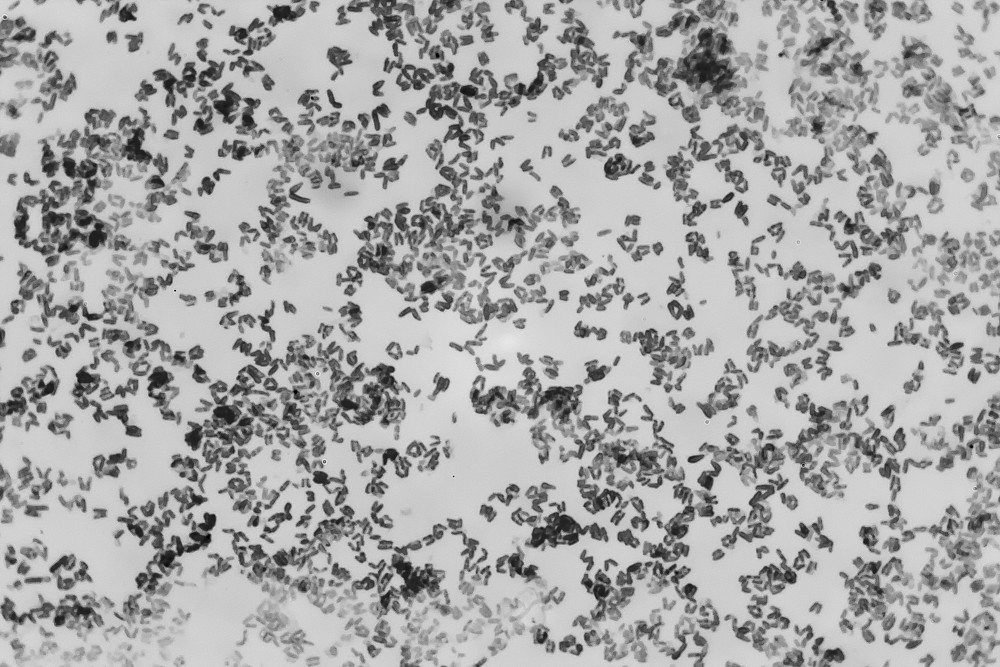

Die Diphtherie wird durch Corynebakterien-Arten verursacht, die zur Bildung des Diphtherietoxins befähigt sind. Der klassische Erreger der Diphtherie ist das Corynebacterium diphtheriae, ein grampositives Stäbchen mit einer polständigen Auftreibung, die ihm eine keulenförmige (trommelschlegelartige) Anmutung verleiht. Die Stäbchen sind zwischen  0,3 - 0,8 Mikrometer breit und etwa 1 - 6 Mikrometer lang, geißellos und damit nicht eigenbeweglich. Der Erreger ist lichtmikroskopisch sichtbar (Abb.4.1), aber von non-pathogenen Corynebakterien (Abb.4.2) auf diesem Wege nicht sicher unterscheidbar. Im Ausstrich werden die Stäbchen oftmals V - oder Y - förmig zueinander liegend gesehen [13,14,15,16,32].

Abb.4.1  Corynebacterium diphtheriae in der Polkörperchenfärbung nach Weigert. Deutlich sichtbar sind die endständigen Auftreibungen und die Lagerung der Stäbchen in V- oder Y-Form. (Abbildung aus: Hegler, Lehrbuch der Infektionskrankheiten. 2. Auflage; Berlin, Springer 1924, Seite 393. Dem Springer-Verlag danke ich für die freundliche Genehmigung zur Verwendung der Abbildung)

Abb.4.2 Corynebacterium pseudodiphtheriae. Ein nonpathogener Erreger. Beachtenswert ist auch hier die V-förmige Lagerung der Stäbchen; im Vergleich zu Abbildung 4.1 zeigt sich die Problematik der mangelnden mikroskopischen Unterscheidbarkeit pathogener und nonpathogener Corynearten. Das Präparat stammt aus meiner Sammlung. Objektiv Leitz PL APO 100x, Okular GW 10x.